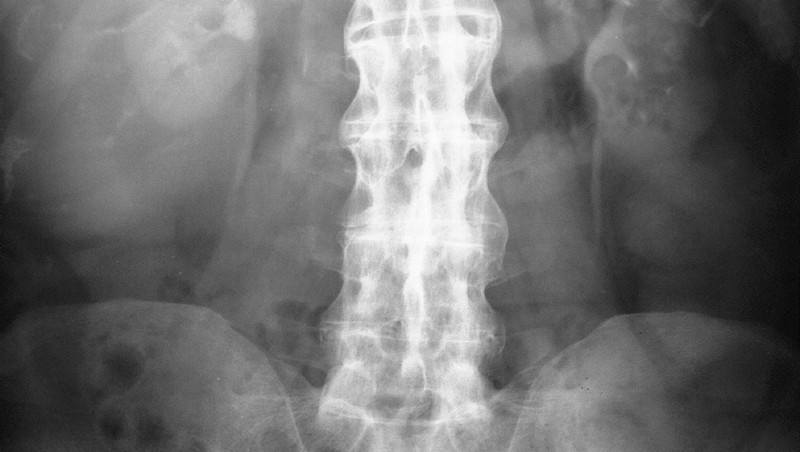

Основанием для выставления диагноза становятся данные внешнего осмотра пациентки, ее жалобы, результаты инструментальных и биохимических исследований. Женщина также направляется к ортопеду и неврологу для консультации. На полученных рентгенографических изображения отчетливо просматриваются характерные признаки дегенеративно-деструктивной патологии:

- эрозии субхондральной (подхрящевой) кости;

- склеротические изменения, частичный анкилоз;

- сращения крестцово-подвздошных сочленений.